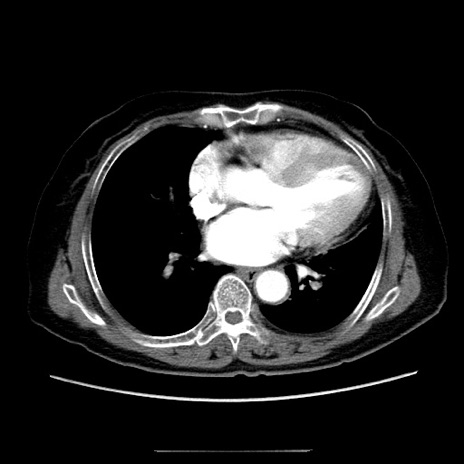

症例5(横断像)

【症例】70歳代女性

【主訴】お腹が張る

【現病歴】1週間くらい前から腹部膨満の自覚あり。昨日夜から増悪したため、本日救急外来受診。

【身体所見】意識清明、BT 36.5℃、BP 165/106mmHg、HR 80bpm、SpO2 98%、腹部:膨満、軟、自発痛・圧痛なし、触診にて不快感あり、腸蠕動音:減弱

【データ】WBC 12600、CRP 1.04